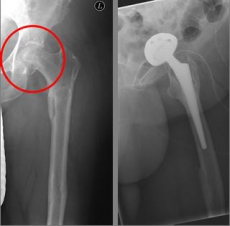

In older age and with stronger displacement of the fracture can be done by a duo-head prosthesis. Here only the femoral head is replaced, the hip socket is preserved. In case of simultaneous hip arthrosis, a total endoprosthesis (hip replacement) with replacement of the acetabular cup can be used.

Picture: In this case, there was already a wear of the hip joint and the affected patient was relatively young, so that a cement-free total endoprosthesis (TEP) of the hip was selected for the treatment of the femoral neck fracture. Here, in addition to the femoral head, the acetabular cup was replaced by an implant.